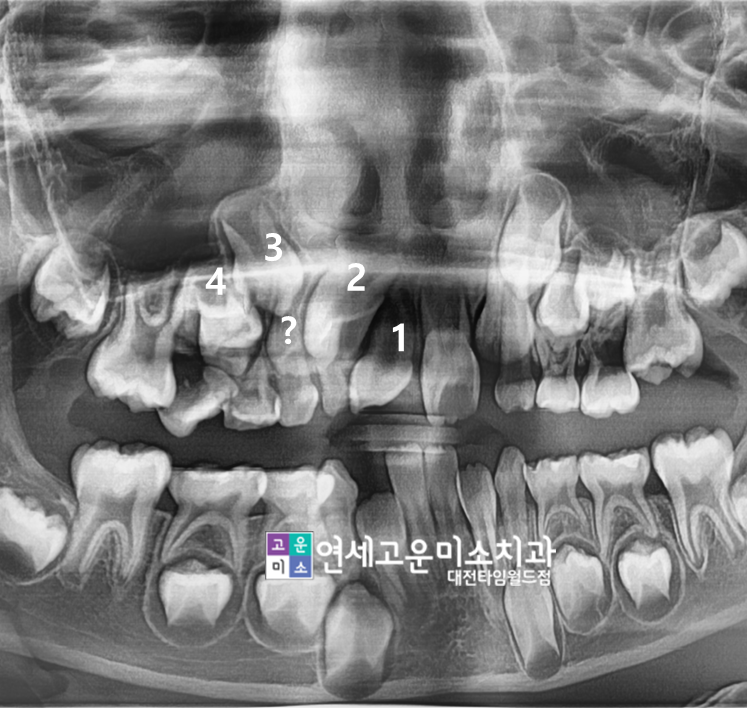

일단 상악 우측 첫번째 앞니(1번 표시 치아)

모양이 기형치인 것을

입안사진에서 알 수 있었습니다.

엑스레이를 보면

쓰러져 있는 유치 밑에

5번치아(제2소구치)가 보이지 않고

2번과 3번 사이에 치아가

하나 더 보이는데 (? 표시된 치아)

5번치아가 저 사이로 난것인가

하는 생각도 들기도 했습니다.

만약 저런 상황이 맞다면

1번 치아는 나중에 씌워야되고

5번자리는 임플란트를 하거나

각각 엉뚱한 자리에 치아를 배치해야 되는

상황도 될 수 있을거 같아서 처음 봤을때

막막하다는 생각도 들었습니다.